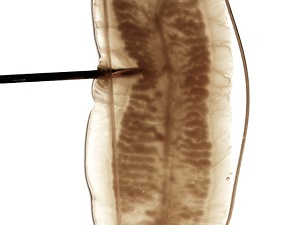

Figure B